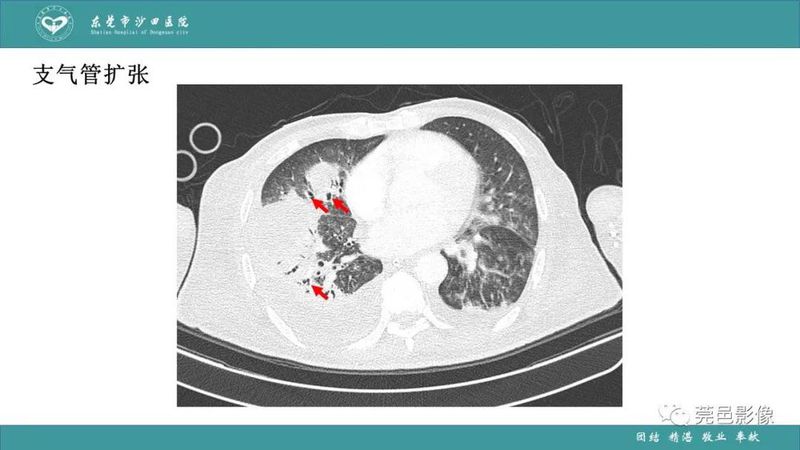

「肺炎克雷伯杆菌肺炎」影像学诊断+鉴别诊断